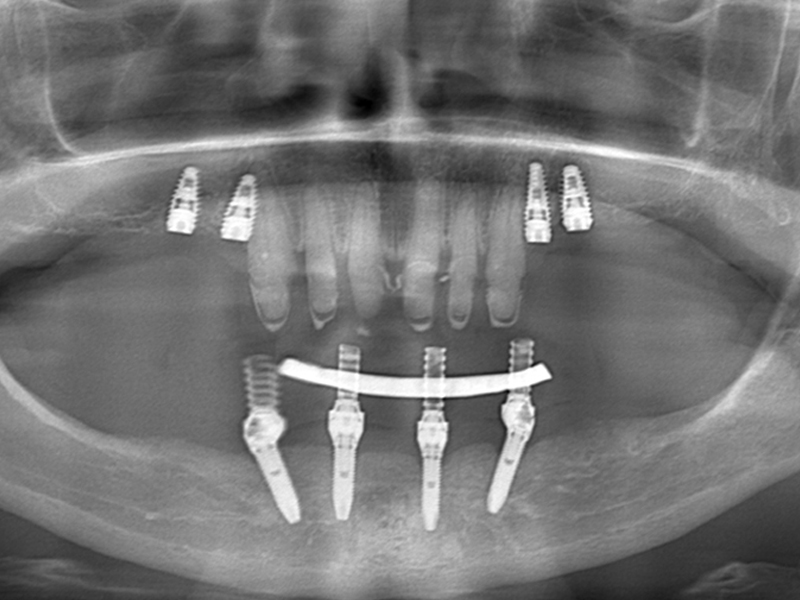

Using the All-On – 4 method; Dental implants are inserted in the same day and in a few hours, a temporary but fixed prosthetic job is performed immediately which will remain until the implants are perfectly integrated into the bone. After about 4-6 months, definitive prosthetic rehabilitation will be performed, which will be screwed onto existing implants. The screw fixing will allow you to remove the restoration (fixed bridge) when necessary.

The specificity of this procedure is that the teeth are fixed on four implants. Thanks to the particular method of inserting the implants, bone reconstruction is not necessary, which is instead a requirement when it is necessary to reconstruct in patients who have total tooth loss.